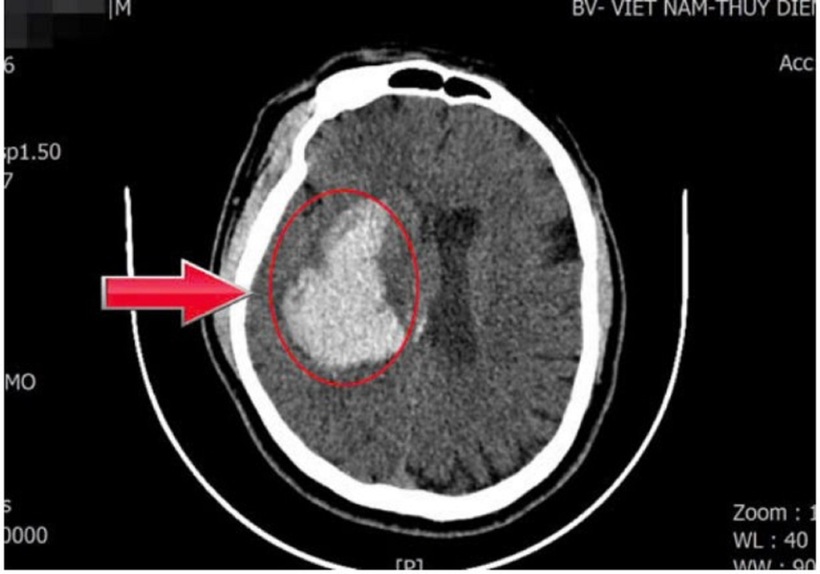

Hình chụp phim não của nam bệnh nhân. Ảnh: VietNamNet.

Ngay sau khi tiếp nhận, các bác sĩ đã tiến hành chụp CT sọ não cấp cứu. Kết quả cho thấy bệnh nhân bị xuất huyết não kèm tụ máu trong nhu mô não, gây chèn ép các tổ chức não xung quanh. Trước diễn biến nặng và nguy cơ đe dọa tính mạng của người bệnh, ê-kíp đã nhanh chóng hội chẩn và quyết định phẫu thuật cấp cứu lấy khối máu tụ.